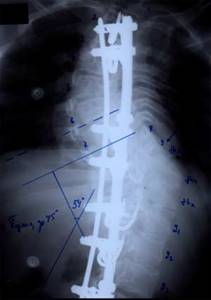

| Больной П-ко, 15 лет Поясничный сколиоз III степени |

Результат оперативного лечения |